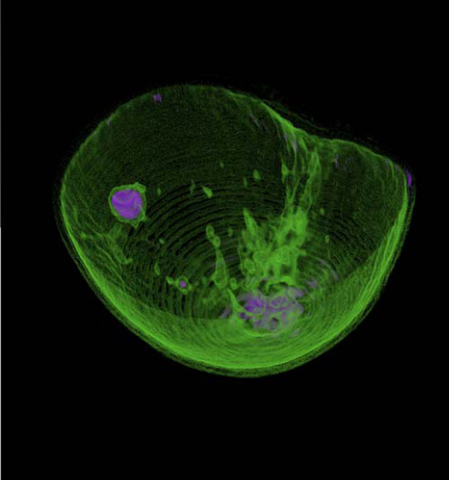

• 3D breast image

3D breast image

New technology is developed by Techniscan and pending FDA approval. It is a 3 D Hologram of breast obtained from 3 different ultrasound images. The system rotates around every 2 Degrees and sends waves to the receiver on the other side of the breast. Volumetric image is created using the measurments of the ultrasound reflection, sound

attenuation and speed of sound.